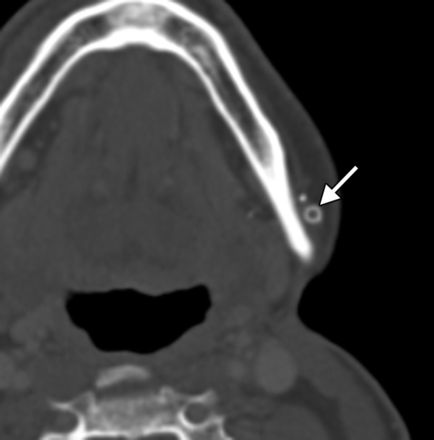

Brow ptosis can be addressed by performing a brow lift. Several methods exist to elevate the brow, one of which consists of implanting a fixation device into the frontal calvaria to which a permanent suture is secured (Fig 1).1 Brow lift can be performed in conjunction with ablation of the brow depressor muscles and blepharoplasty. Numerous fixation devices can be used, including pins, screws, tacks, K-wires, and tissue adhesives. Metallic fixation devices can be depicted on CT and should not be mistaken for unintended foreign bodies (Fig 2).

Brow lift. Axial CT image shows a metallic left frontal bone pin (arrow) used for suture fixation.